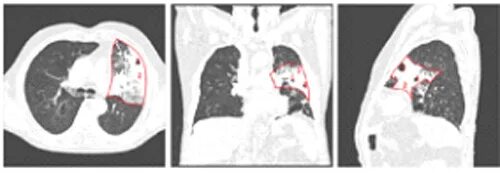

Как выглядит пневмония на кт